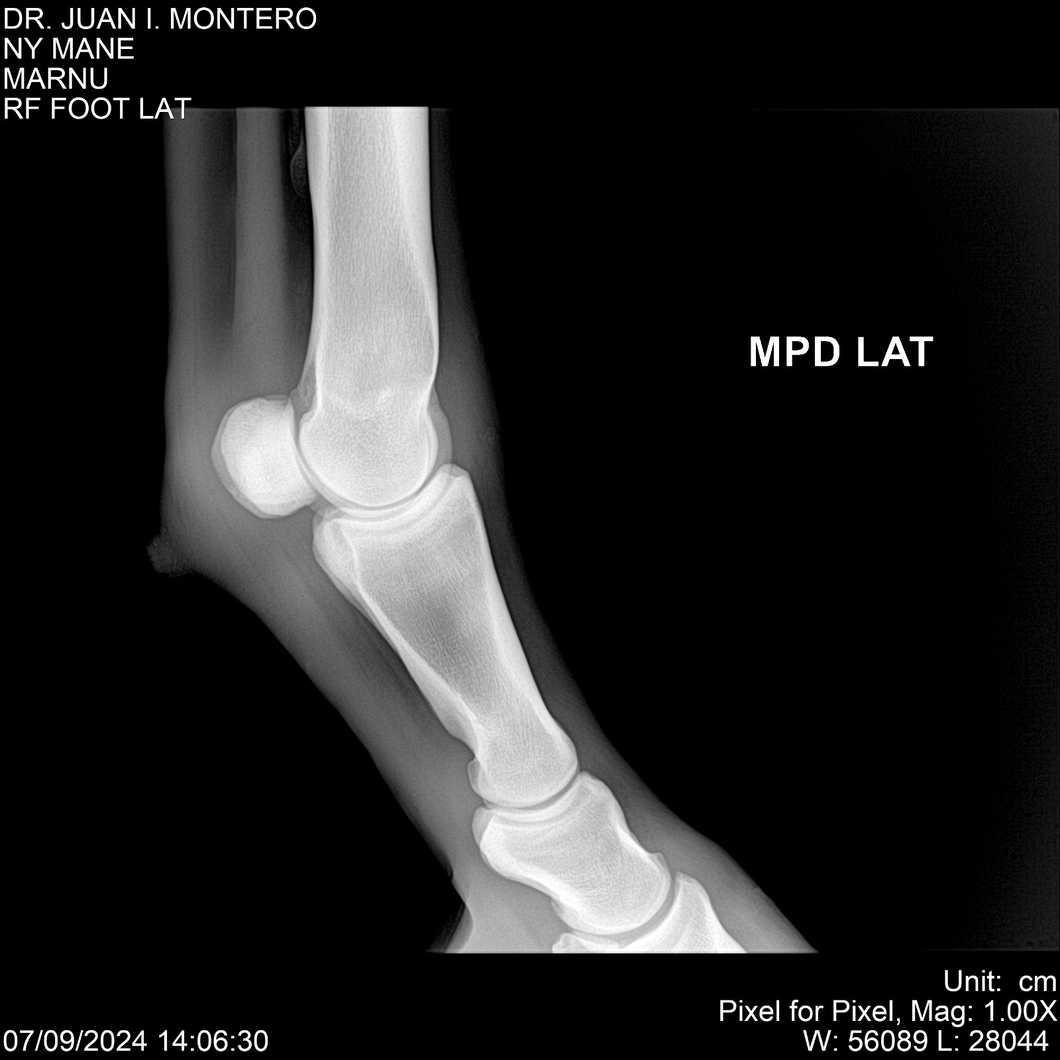

LOTE 20, NY MANE Lote Anterior Volver al remate Lote Siguiente Ficha Contacto Montevideo - Ficha del Lote Identificador: #282520 Categoría: Yeguarizos 76 Visualizaciones ClicData Contacto Empresa: Abelenda N. R., Walter Hugo Nombre*: Teléfono* : E-mail* : Mensaje Enviar Registrese gratis Este contenido Exclusivo está disponible sólo para usuarios registrados Ingresar